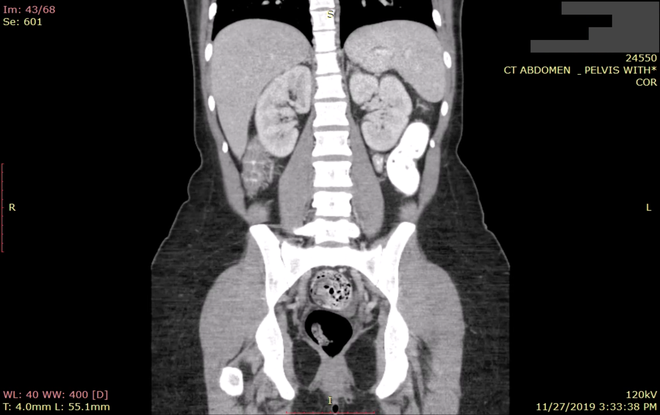

Mỗi ngày, hàng triệu hình ảnh ngành y chứa thông tin sức khỏe của cá nhân người bệnh rò rỉ ra khắp Internet. Hàng trăm bệnh viên, cơ sở y tế và trung tâm xử lý hình ảnh đang sử dụng những hệ thống lưu trữ không an toàn, mở ra lỗ hổng cho phép bất kỳ ai có kết nối Internet đều có thể truy cập. Cơ sở dữ liệu chứa hàng tỷ hình ảnh mang thông tin nhạy cảm đang được che đậy một cách sơ sài.

Khoảng một nửa số hình ảnh đó - bao gồm ảnh X-quang, ảnh siêu âm và ảnh cắt lớp - thuộc về bệnh nhân trên đất Mỹ. Số ảnh còn lại thuộc bệnh nhân khắp thế giới.

Greenbone Networks sở hữu nhiều tài liệu khẳng định sự tồn tại của vấn đề nhức nhối này. Những con số cụ thể gồm có: 24 triệu xét nghiệm và tài liệu khám chữa bệnh chứa tổng cộng 720 triệu hình ảnh rò rỉ hồi tháng Chín vừa qua. Hai tháng sau thời điểm đó, số lượng hình ảnh rò rỉ đã tăng lên gấp rưỡi - khoảng 35 triệu bài xét nghiệm đã rò rỉ, để lộ tổng cộng 1,19 tỷ hình ảnh chụp liên quan tới người bệnh.

Các nhà nghiên cứu nói rằng nguồn gốc vấn đề nằm tại các yếu điểm vẫn có trên server lưu trữ, vốn được bệnh viện, văn phòng bác sĩ, các trung tâm dữ liệu lưu trữ hình ảnh y khoa sử dụng. Hầu hết các cơ sở y tế lưu dữ liệu bệnh nhân với định dạng tệp cũ vài thập kỷ (và cũng là quy chuẩn ngành) mang tên DICOM, mục đích là để lưu được hình ảnh y khoa chỉ nội trong một file và dễ dàng chia sẻ giữa các cơ sở y tế.

Một người có thể xem hình ảnh lưu trữ dưới dạng DICOM với bất cứ ứng dụng miễn phí nào. Các hình ảnh DICOM được lưu trong hệ thống sao lưu và liên lạc, được gọi là server PACS, cho phép lưu và chia sẻ dễ dàng. Tuy nhiên, đa số các cơ sở y tế bỏ qua bước đặt mật khẩu cho server PACS, cứ thế kết nối nó với Internet.

Những server hớ hênh trước con mắt nhòm nhó của bất cứ ai, các thông tin nhạy cảm của bệnh nhân có thể rơi vào tay bất cứ ai có kết nối Internet. Những tấm phim chụp còn kèm theo cả tên tuổi, ngày sinh bệnh nhân cùng với những chẩn đoán bệnh (nhiều khi là nhạy cảm). Có một số bệnh viện Mỹ còn dùng số an sinh xã hội để xác định danh tính bệnh nhân cho dễ.